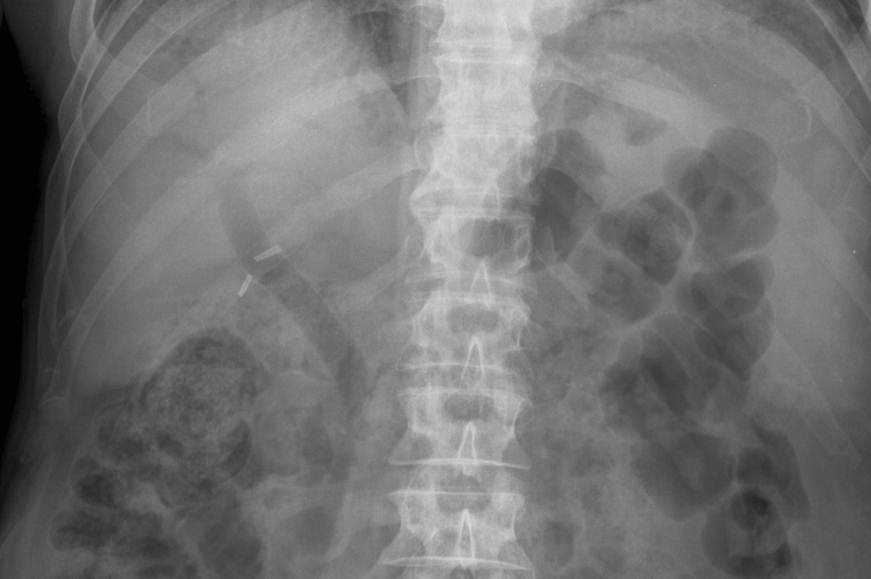

Calcified Gall stone

What can you see here? What is the likely cause?

Cholecystectomy clips - and air in the Biliary tree. The most likely cause is recent laprop surgery.